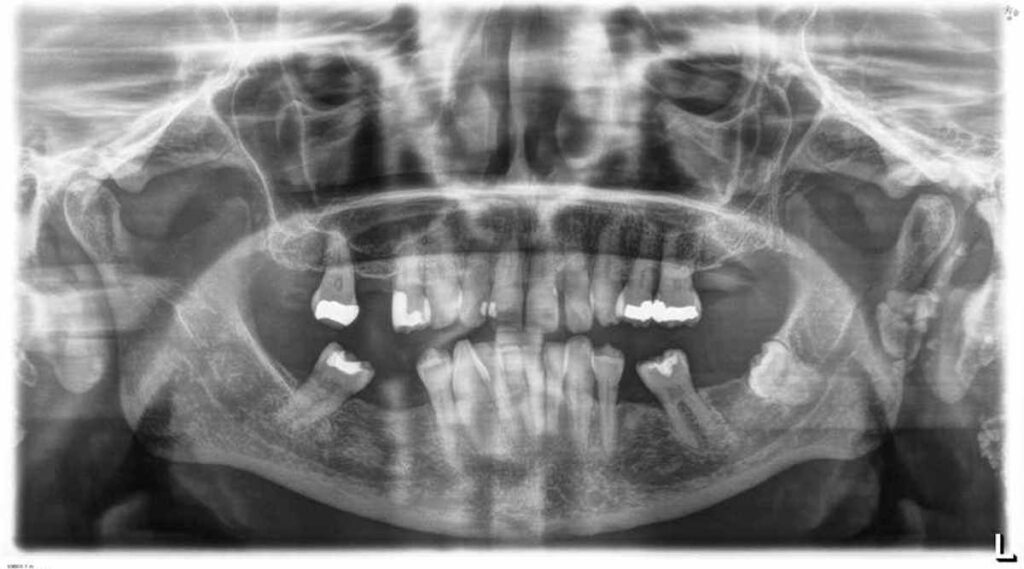

8-year-old boy with bleeding gums and fever

An 8-year-old boy presented to the local hospital emergency room with his mother, having been referred by a general dentist due to bleeding gums. H…

7-year-old boy with bone loss and gingival retraction

A 7-year-old boy was referred with his parents to the pediatric dentist by a family dentist for evaluation due to bone loss and gingival retractions.

6-year-old boy with bleeding gums and fever

A 6-year-old boy presented to the local hospital emergency room with his mother with "bleeding gums" and fever.